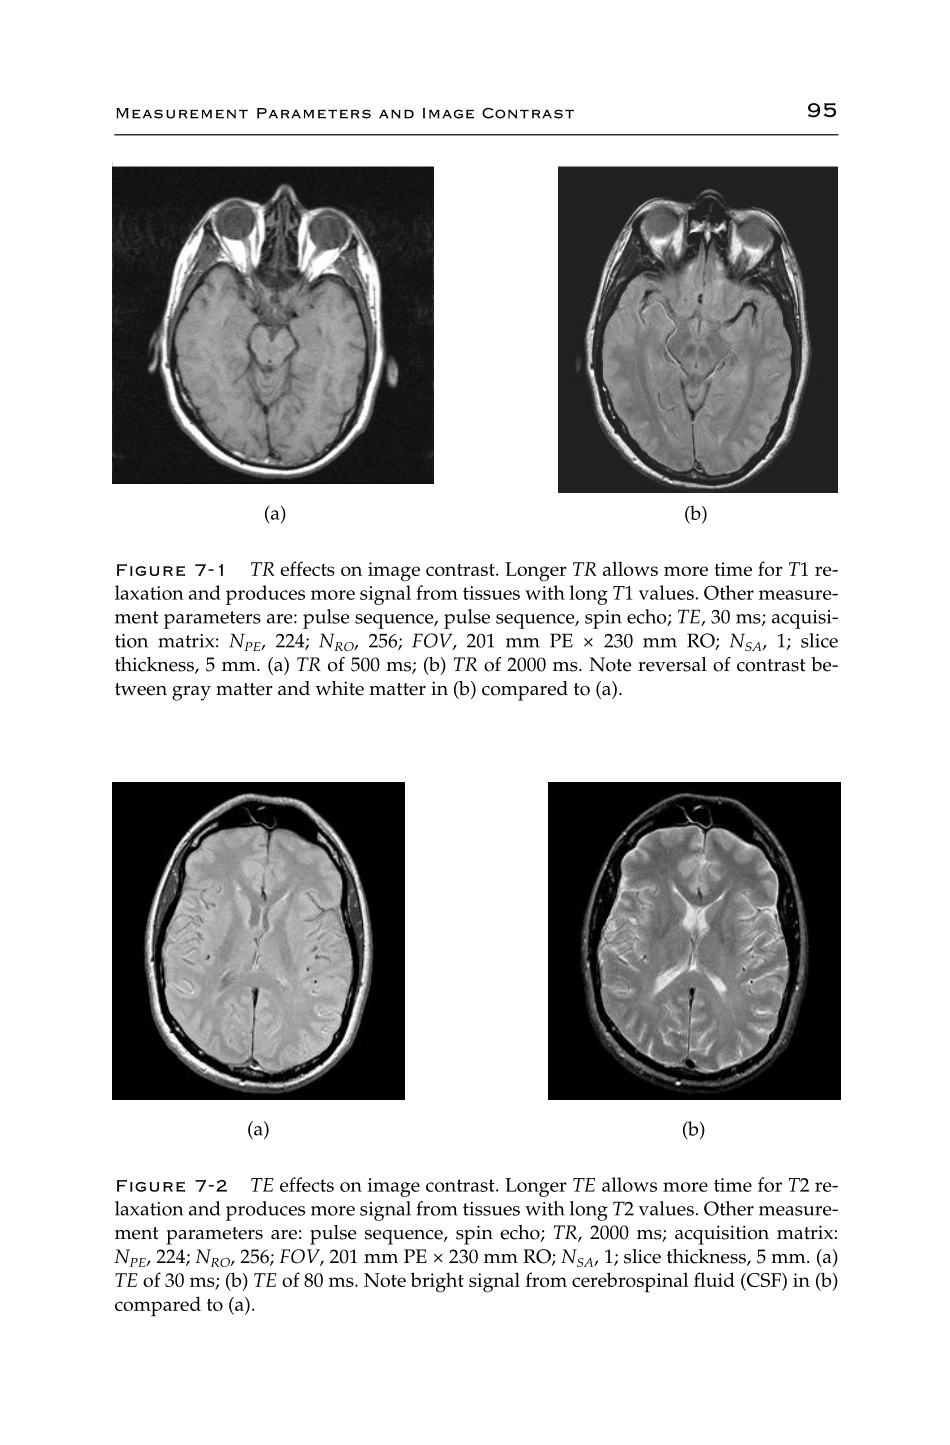

CHAPTER7MeasurementParametersAndImageContrastAsmentionedinChapter6,manyofthemeasurementparametersofapulsesequencemaybemodifiedthroughtheuser-interfacesoftware.Theparticularparameterswillbedetermine...